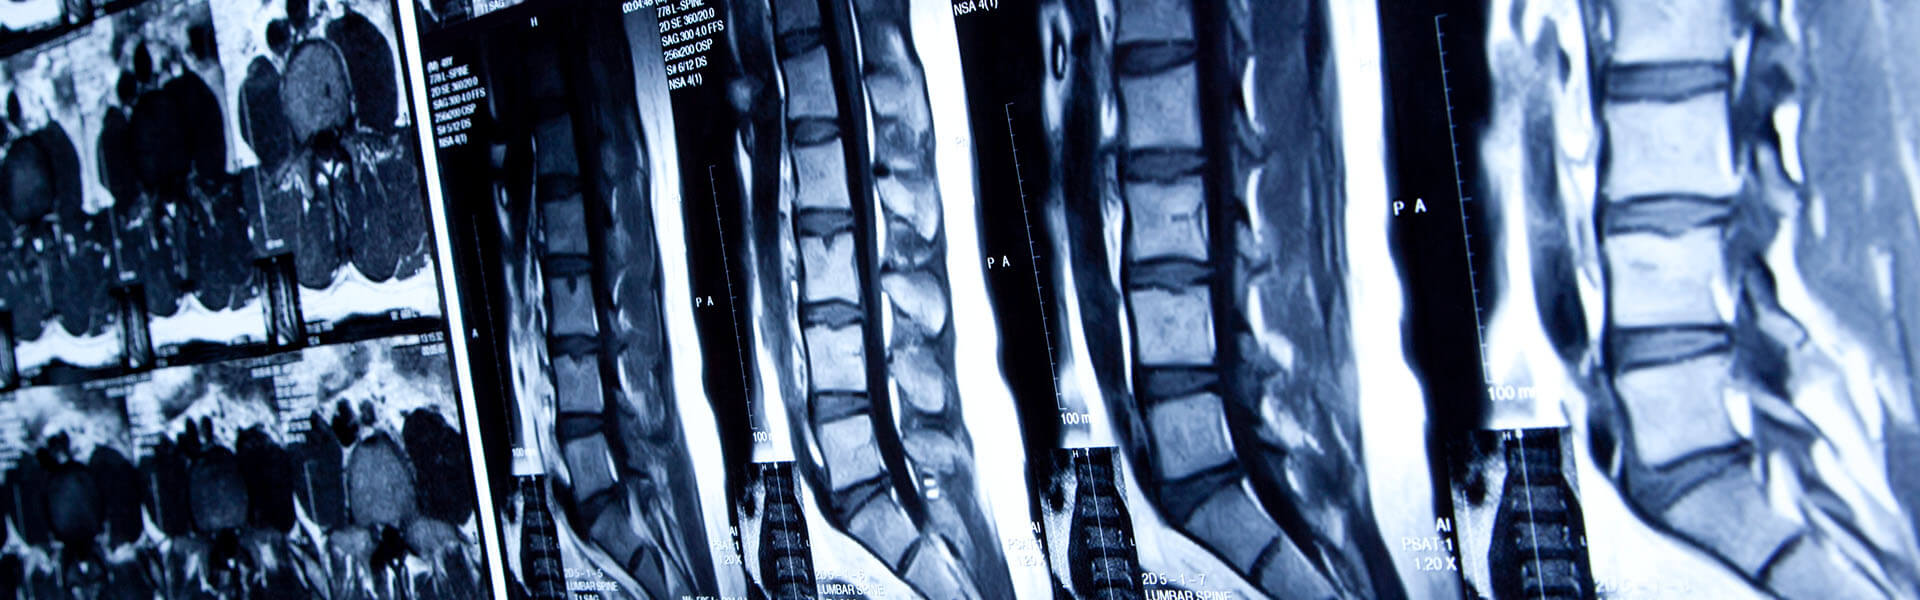

An accident that causes a back injury can leave you with terrible pain and recurring physical problems. Damage to your back can take an especially long time to improve, and it can also result in pain and harm to other parts of your body over time. These injuries often keep people from work or school for much longer than one would assume, and you may have a very difficult time resuming activities that you once took for granted. Winning the compensation that you deserve after suffering a serious back injury will require a knowledgeable spinal cord injury lawyer who knows how to prove your injuries and the effect they will have on your life. At Paul Padda Law, we have decades of experience helping victims of accidents who are suffering from complex and chronic pain and disabilities. We know how to identify all of your injuries, and what it will take to secure the recovery and compensation that you deserve.

More About PaulYour spinal column can be badly damaged if you sustain a significant collision or fall. This body part is made up of your spinal cord which is surrounded by segmented vertebrae bones that are separated by soft discs. The spinal cord is an important part of your nervous system that transmits sensory information between your brain and limbs. Damage to your spinal column can be very difficult to heal, and it can affect different limbs and organs throughout your body. Given the complexity of this part of your body, it can be hard to know exactly what damage you have suffered.

A spinal cord injury often requires years of treatment and rehabilitation. Obtaining damages from a negligent party requires having a back injury lawyer who understands the many ramifications of spinal cord damage. Issues of back pain after a car accident, or paralysis after a workplace fall, are unique in every case. Paul Padda Law has helped victims in many spinal cord injury cases.